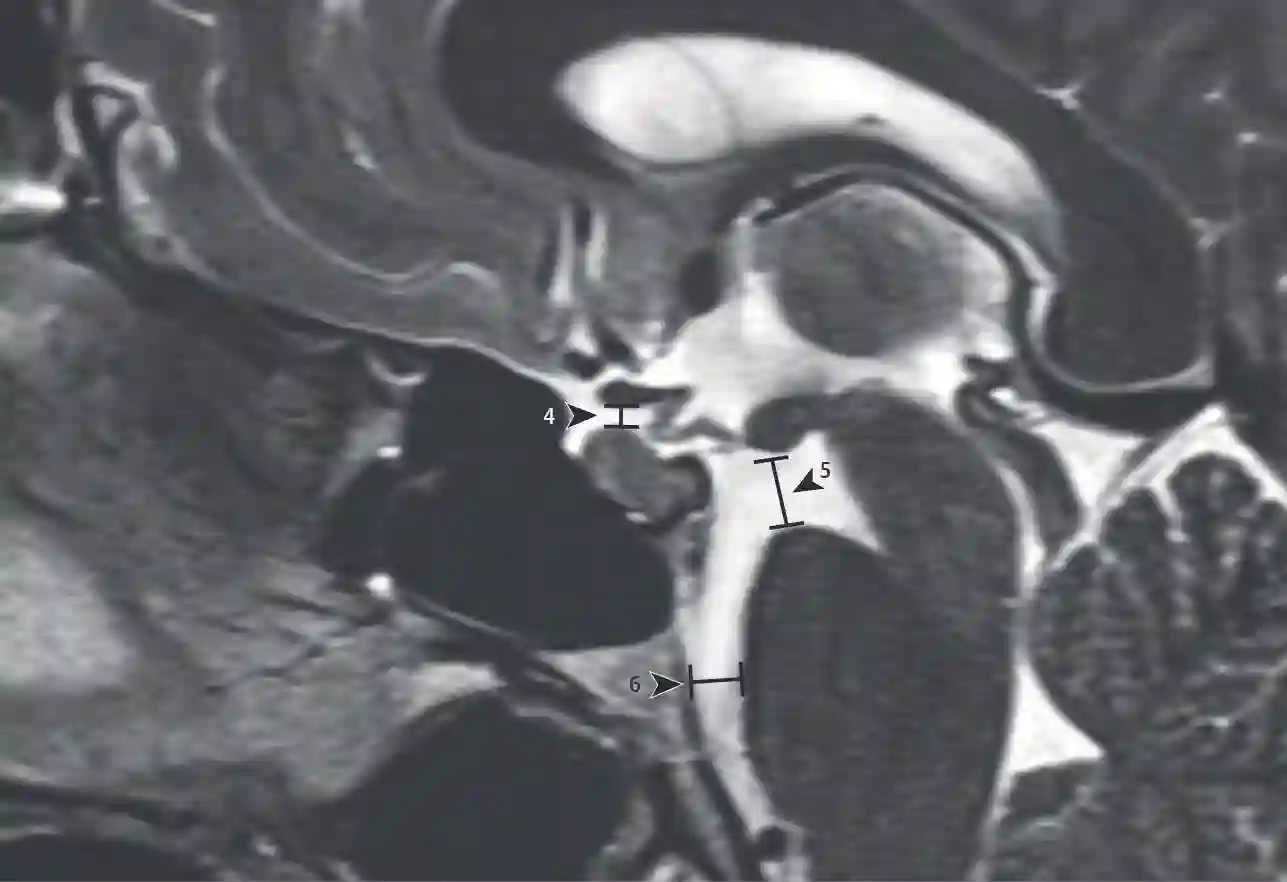

SIH Score MRT

4) Distanz der suprasellären Zisterne 5) Pontomammilläre Distanz 6) Präpontine Zisterne. Abbildung adaptiert von Dobrocky T. et al. 2019. JAMA Neurology.